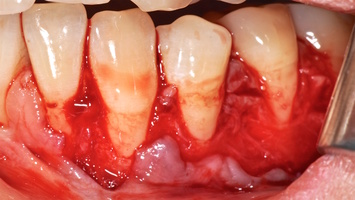

1. Генерализованные рецессии в области нижней челюсти оперировались в один этап все 12 зубов, фронтальный участок с аутотрансплантатом от 3.2 до 4.2 зубов. А дистальные участки от 3.6 до 3.3 и от 4.6 до 4.3 зубов с использованием пластического материала ТМО (dura mater) (рис. 4а-з).

4. Этапы хирургического лечения рецессий десны на нижней челюсти

3.2-4.2 зубы были прооперированы методом, сочетающим вестибулопластику с одновременным увеличением ширины и толщины прикрепленной десны при помощи свободного десневого аутотрансплантата (операция Bjorn, 1963 г.).

1. Подготовка принимающего ложа. Включает в себя формирование полнослойно-расщепленного слизисто-надкостничного лоскута (полнослойного в области зенитов рецессий, расщепленного билатерально области рецессии десны), рассечение и отслаивание слизисто-мышечных волокон вестибулярно ниже мукогингивальной границы, деэпителизация межзубных сосочков.

2. Обработка поверхностей корней зубов. Включает ультразвуковую обработку скейлером для очищения от минерализованных зубных отложений и мягкого зубного налета, экспозицию геля ЭДТА 17% в течение двух минут, механическое удаление слоя бесклеточного цемента импрегнированного микроорганизмами зоноспецифическими кюретами, полировку пародонтологическими борами («фасолька» и «обратный треугольник»).

3. Получение аутотрансплантата: начинается с определения толщины донорской зоны и замеров размера будущего трансплантата. Зона забора от второго премоляра до третьего моляра верхней челюсти. Глубина погружения брюшка скальпеля 2 мм, далее трансплантат оптимизируют — деэпителизируют по периметру.

4. Затем проводиться позиционирование аутотрансплантата в области рецессий и принимающего ложа двумя-тремя узловыми швами; после аутотрансплантат стабилизируют прижимающими двумя-четырьмя матрасными крестообразными швами, что позволит плотно прижать аутотрансплантат и избежать образования «мертвых» зон для питания аутотрансплантата.